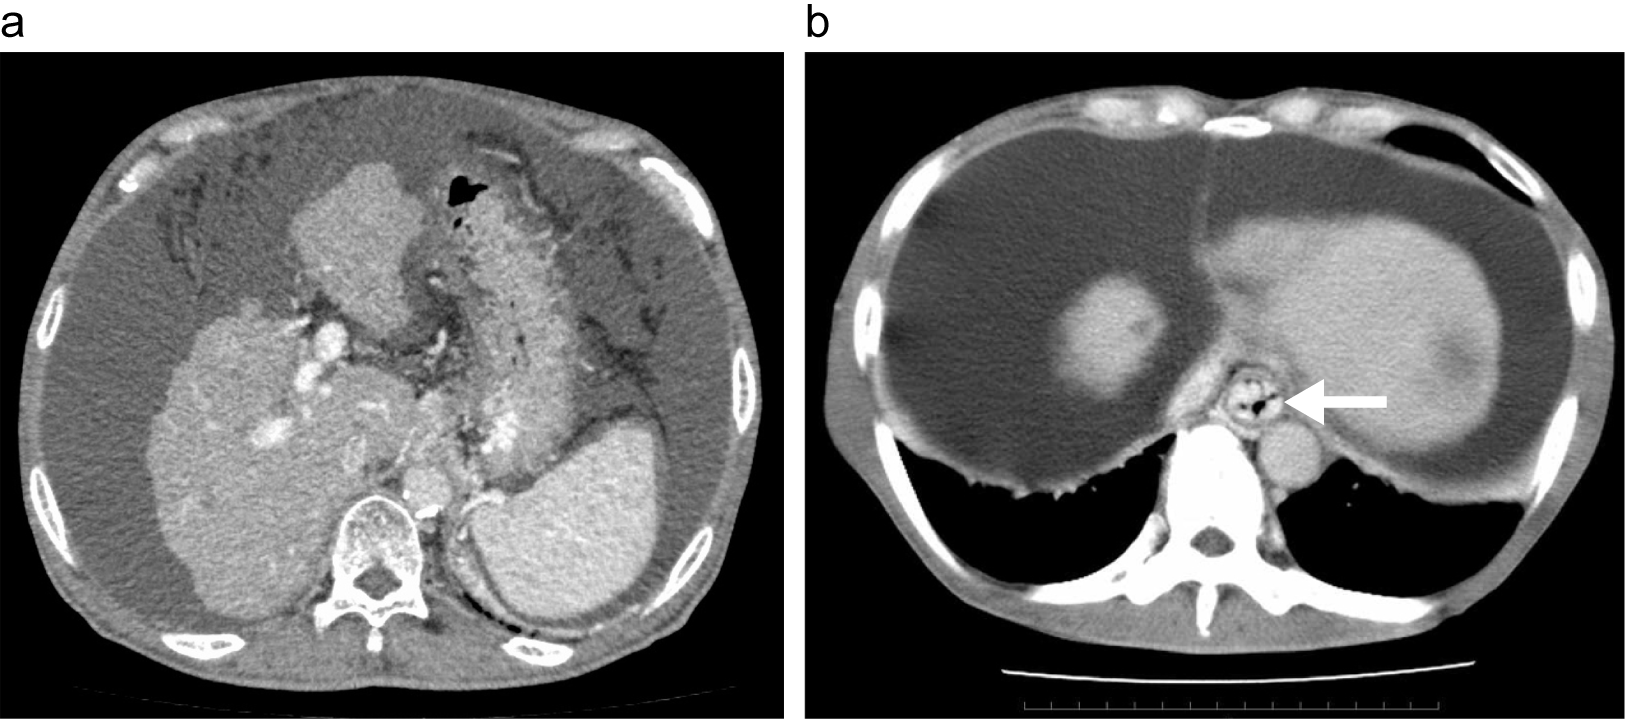

腹部CT(造影)

a: 典型的な肝硬変、門脈圧亢進症のCT。肝萎縮、表面凹凸、脾腫、多量の腹水を認める。

b: 下部食道の内腔に造影される静脈瘤を認める(矢印)。多量の腹水を認める。

出典

img

1: 著者提供